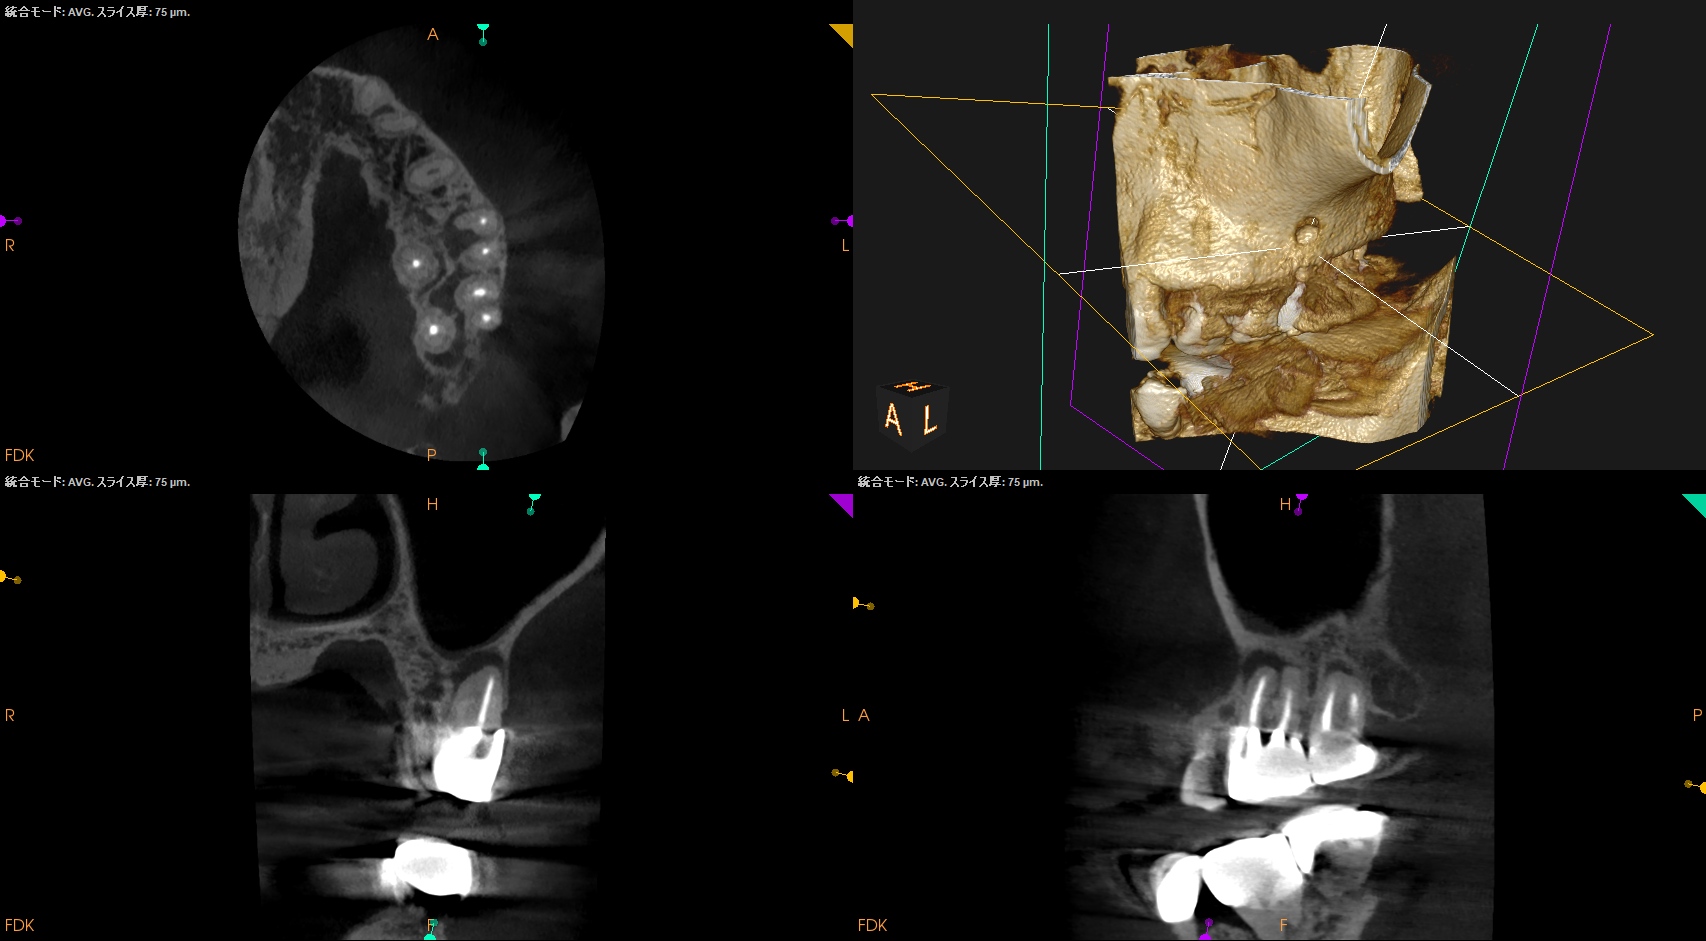

#14 MB Apicoectomy(2025.4.14)

MBのApexを発見した。

ここを3mm切断した。

Retroprep, Retrofillingした。

術後にPA, CBCTを撮影した。

後日、築造するがその後のPAが以下だ。

MB

B

逆根管充填材は逆根管形成で穿孔させたが即日修復=充填しているので問題ないだろう。